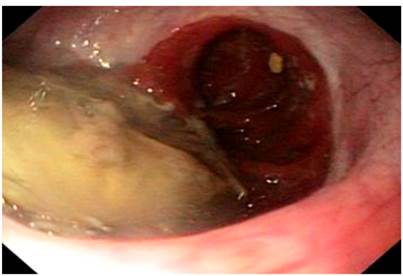

Durante el examen físico se evidenciaron signos de deshidratación, sin otros hallazgos positivos. En vista de los antecedentes y los síntomas descritos, se decidió realizar una endoscopia de las vías digestivas altas. En ella se observó una impactación alimentaria a nivel de la anastomosis esofagoyeyunal (Figura 1). Se efectuó la extracción de un cuerpo extraño y se halló una anastomosis, sin signos de recaída tumoral. Sin embargo, se encontró una zona de estenosis del 40 % de la luz, a 10 cm de la anastomosis, con una disminución concéntrica de la luz por un edema circunferencial de la mucosa (Figura 2), lo que permitió el paso del equipo con una ligera resistencia, y se tomaron biopsias de dicha zona.